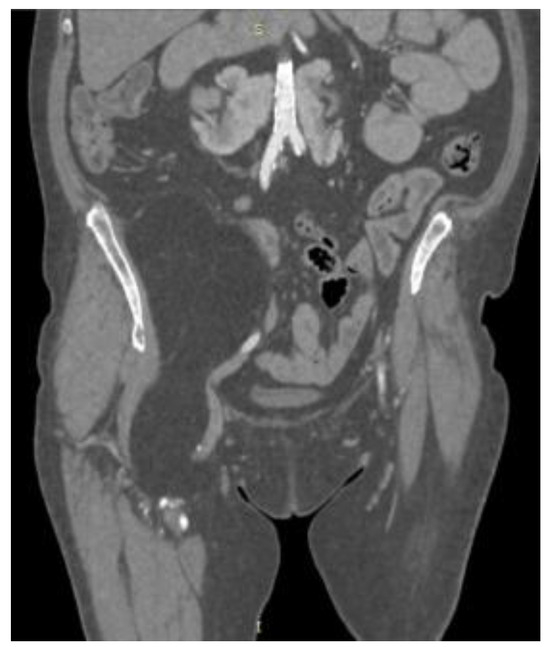

2. Case Presentation